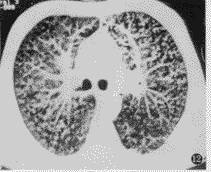

图12 弥漫性泛毛细支气管炎。支气管血管束增粗,但以小叶核分支状影增多为主

支气管血管束末梢显示率增加主要为小叶核支气管血管束异常所致。Gruden等[4]认为,小叶核分支状影增多,病理基础为细支气管扩张,腔内充满黏液;而小叶核不规则结节或磨玻璃状密度结节为细支气管周围炎性病变或支气管血管束周围结节所致。我们在小叶核影增大的病理对照中,慢性支气管炎、癌性淋巴管炎及煤工尘肺均可见小叶核影增大,但有不同的病理基础,仅根据此征象鉴别诊断困难。而小叶核分支状影增多的病理基础为细支气管扩张及其周围炎,为小叶细支气管及其周围病变表现。

沿支气管血管束分布的支气管或肺实质病变,表现为沿支气管血管束分布的小斑片状影,支气管可较相邻肺动脉增粗。支气管壁增厚而相邻肺动脉正常,多提示不合并有周围肺间质异常。在伴随有细支气管病变时,小叶核分支状影明显增多,本组以支气管为主的弥漫性肺疾病患者中,70%有此征象。